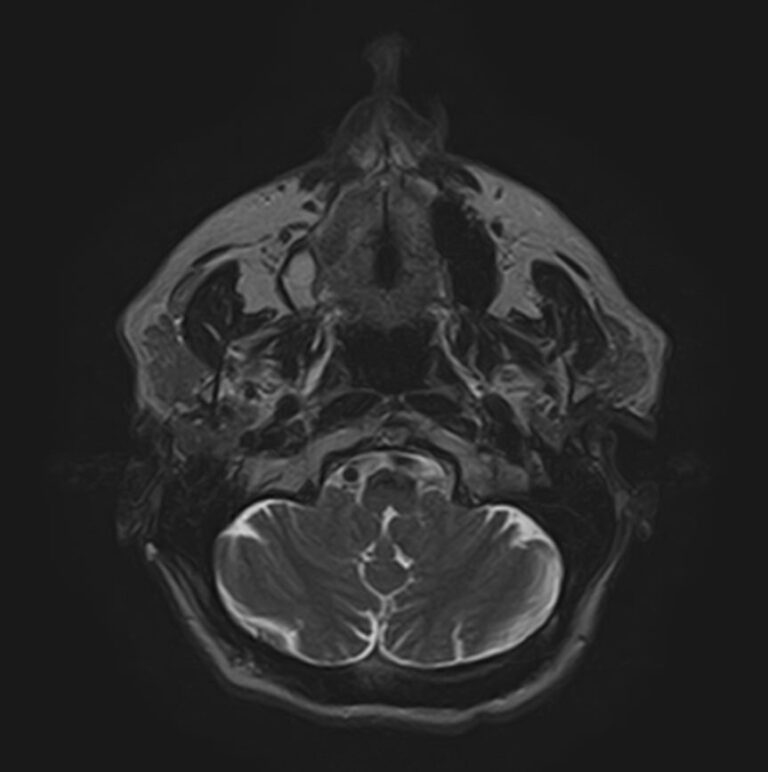

Магнитно-резонансная томография мягких тканей широко используется для детальной визуализации мягкотканных структур.

С помощью МРТ можно оценить состояние мышц, фасций, межфасциальных пространств, синовиальных оболочек, связок, сухожилий, сосудисто-нервных пучков, лимфоузлов и лимфатических протоков, надкостницы, кожи, подкожно-жировой клетчатки.

В клинике «Доступная медицина» исследование выполняется на современном высокопольном томографе закрытого типа TOSHIBA VANTAGE TITAN 1,5 Тесла, который создает изображения с высокой детализацией мягкотканных структур за счет послойного сканирования в различных плоскостях.